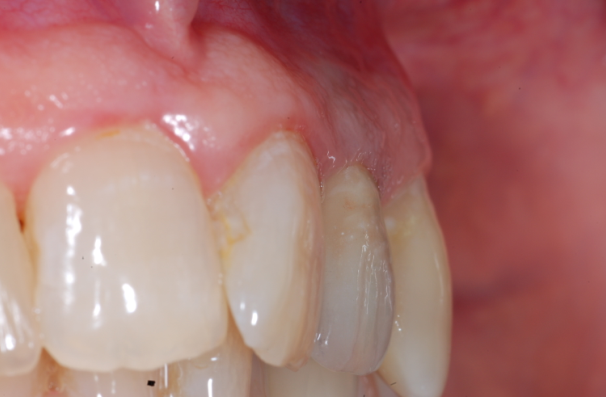

Lo scopo del presente lavoro quello di dimostrare i reali vantaggi che una tecnica delicata, come quella post-estrattiva offre nel riabilitare protesicamente un settore ad alta rilevanza estetica. Il paziente in esame presentava una frattura coronale del 22 devitalizzato, con lesione granulomatosa peri-apicale. Su richiesta del paziente veniva applicata una corona provvisoria e programmato per un impianto post-estrattivo. Le condizioni cliniche del paziente erano buone per cui si procedeva alla pianificazione del caso. Pianificazione che prevedeva, lestrazione del 22 con asportazione del granuloma peri-apicale, disinfezione, cruentazione dellalveolo, ed applicazione di un impianto Nobel-Direct (3.5 x 13 mm). La valutazione intra-operatoria dellaltezza alveolare, della distanza crestale vestibolo-palatale e mesio-distale, facevano propendere per linserimento di un impianto Nobel-Direct della dimensione 4.3 x 13 mm senza fresatura alveolare, ma semplicemente avvitandolo nellalveolo e raggiungendo una forza di serraggio > di 45 N. Preparare il sito implantare per una maggiore profondit avrebbe creato problemi per lasse implantare determinando una eccessiva vestibolarizzazione del moncone. Si procedeva allapplicazione ed alladattamento del provvisorio dopo una piccola correzione del moncone. Nota importante da sottolineare il perfetto adattamento del provvisorio, non solo al pilastro implantare ma anche alla mucosa gengivale, dove soprattutto nellimplantologia post-estrattiva lemergenza dellimpianto non sar mai perfettamente aderente n alla cresta alveolare, quasi sempre a sezione ovalare, n alla mucosa gengivale. Il sigillo mucosale garantisce la formazione ed il mantenimento di quel coagulo ematico che andr a colmare il gap tra osso, impianto e corona, impedendo laccumulo di residui alimentari e di placca, che minerebbero sicuramente questa zona critica. Si comprende pertanto che il provvisorio non deve invadere uno spazio che non gli compete, ma deve occupare sicuramente quello spazio che prima competeva alla corona riproducendo perfettamente gli stessi rapporti con i tessuti limitrofi. Al paziente veniva consigliata una copertura antibiotica (Amoxicillina cpr 1 gr/12 ore x 5 gg,; Efferalgan cpr 1 cpr alloccorrenza; Dentosan collutorio 0,20% - 3-4 sciacqui al die x 10 gg) evitare sovraccarichi masticatori, di poter incidere ma di non strappare i cibi. Il paziente veniva controllato dopo 7 giorni, ad 1 mese ed al terzo mese, periodo questultimo in cui si procedeva ad un controllo rx endorale alla preparazione del pilastro con ribasatura del provvisorio. Dopo circa 7 giorni si rilevavano le impronte di precisione e quindi si finalizzava il lavoro. Possiamo ritenerci soddisfatti del risultato finale, sia clinico, che radiografico ed estetico, considerando le difficolt presentatesi durante lintervento. Tra queste annoveriamo sicuramente lestrazione del residuo radicolare, devitalizzato, con granuloma peri-apicale e lesiguit della corticale vestibolare, che doveva essere assolutamente conservata. Il risultato estetico finale, tessuti molli e corona dentaria, sicuramente soddisfacente, e deriva da una cura minuziosa dei particolari chirurgici e protesici, sempre nel rispetto massimo dei tessuti.

Il paziente in esame stato sottoposto ad estrazione del residuo radicolare del 22 con asportazione di granuloma peri-apicale ed inserimento contestuale di una fixture monofasica (Nobeldirect) con protesi fissa provvisoria. Il caso stato completato con protesi fissa oro-ceramica dopo tre mesi dall'intervento.